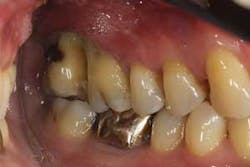

Figures 2a and 2b: Initial presentation in 2011 of the upper right and left molar area, showing advanced bone loss with furcation involvement on the molars.

At presentation, Martin was in his fifties with a medical history significant for controlled hypertension with no known food or drug allergies. He had been lackadaisical with his dental care in the past because of his busy schedule, but he was motivated to get his hygiene and treatment under control. He denied a history of smoking/alcohol/drug use. Based on his full-mouth series (figure 1) and clinical presentation, Martin had generalized, moderate bone loss with localized, severe bone loss in the posterior maxillary right and left quadrants (figures 2a and 2b) as well as the mandibular anterior incisor area (figure 3).